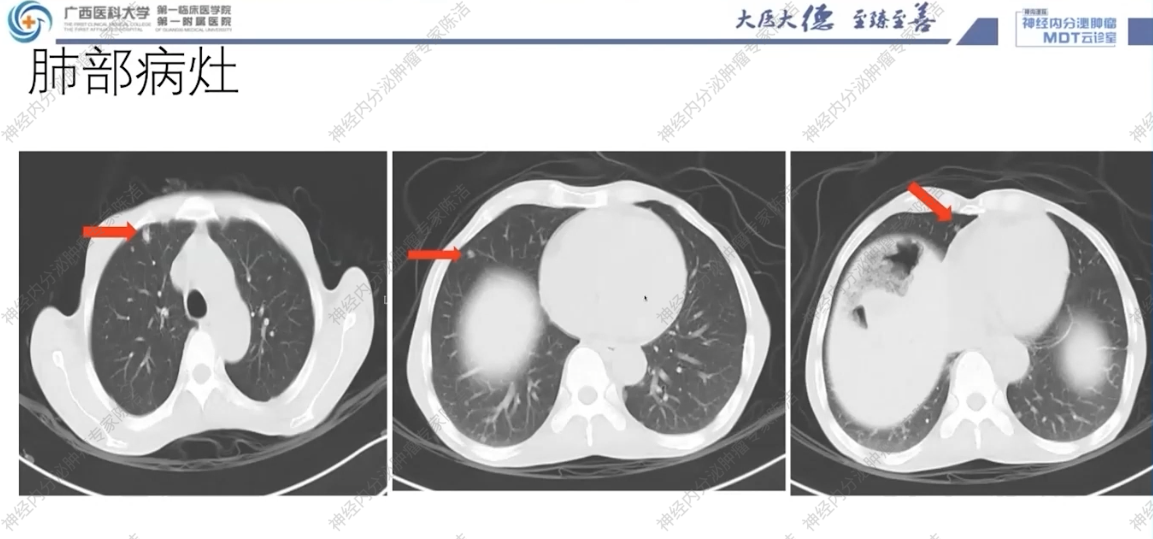

CT:双侧肾上腺占位伴双肺多发结节,考虑恶性嗜铬细胞瘤伴肺转移可能性大;同时可见双肾囊肿、肠郁张、双肺慢性炎症及肺气肿。

影像诊断科汤伟教授:影像学上,患者双肺多发结节,边界清晰,高度怀疑为转移瘤。腹部CT可见肠管明显扩张积气,呈肠梗阻样改变,符合巨结肠的表现。双侧肾上腺可见富血供的占位,符合嗜铬细胞瘤。垂体MRI平扫虽未做增强,但冠状位可见垂体左侧有低信号微腺瘤的可能,建议行垂体薄层动态增强扫描以明确诊断。

后续治疗的挑战:当前最大的挑战是明确肺部和肝脏病灶的性质。虽然病理提示肝脏病灶为转移性NET,且TTF-1阳性指向甲状腺髓样癌来源,但仍需通过对肺部或甲状腺结节的穿刺活检来最终确认。一旦确诊为转移性MTC,患者将有机会从针对RET突变的靶向药物治疗中获益。对于巨结肠,其术前处理与常规的外科原则一致。